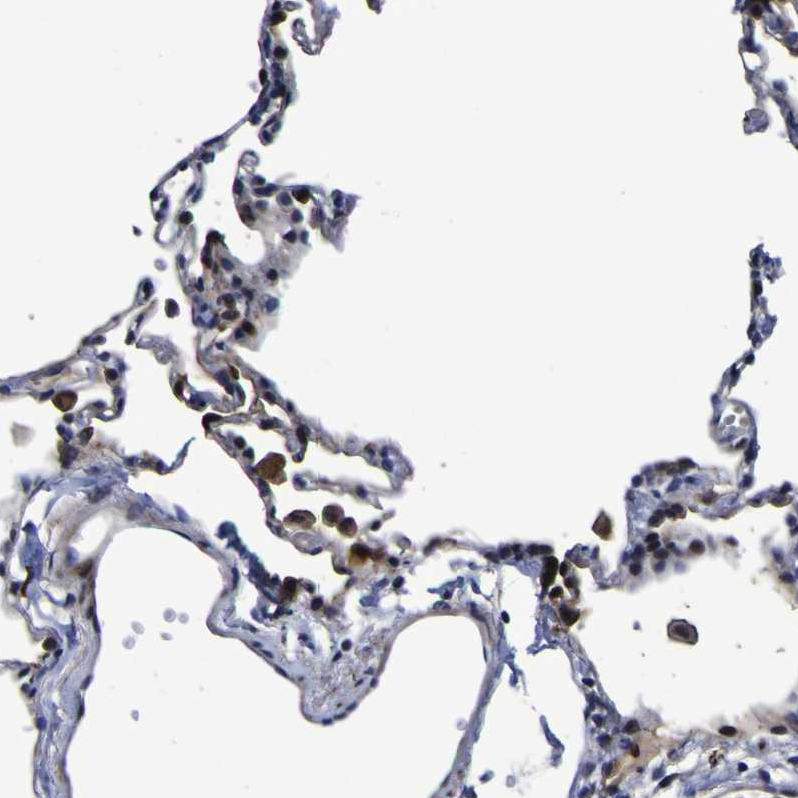

Immunohistochemical staining of human lung shows moderate cytoplasmic positivity in macrophages.